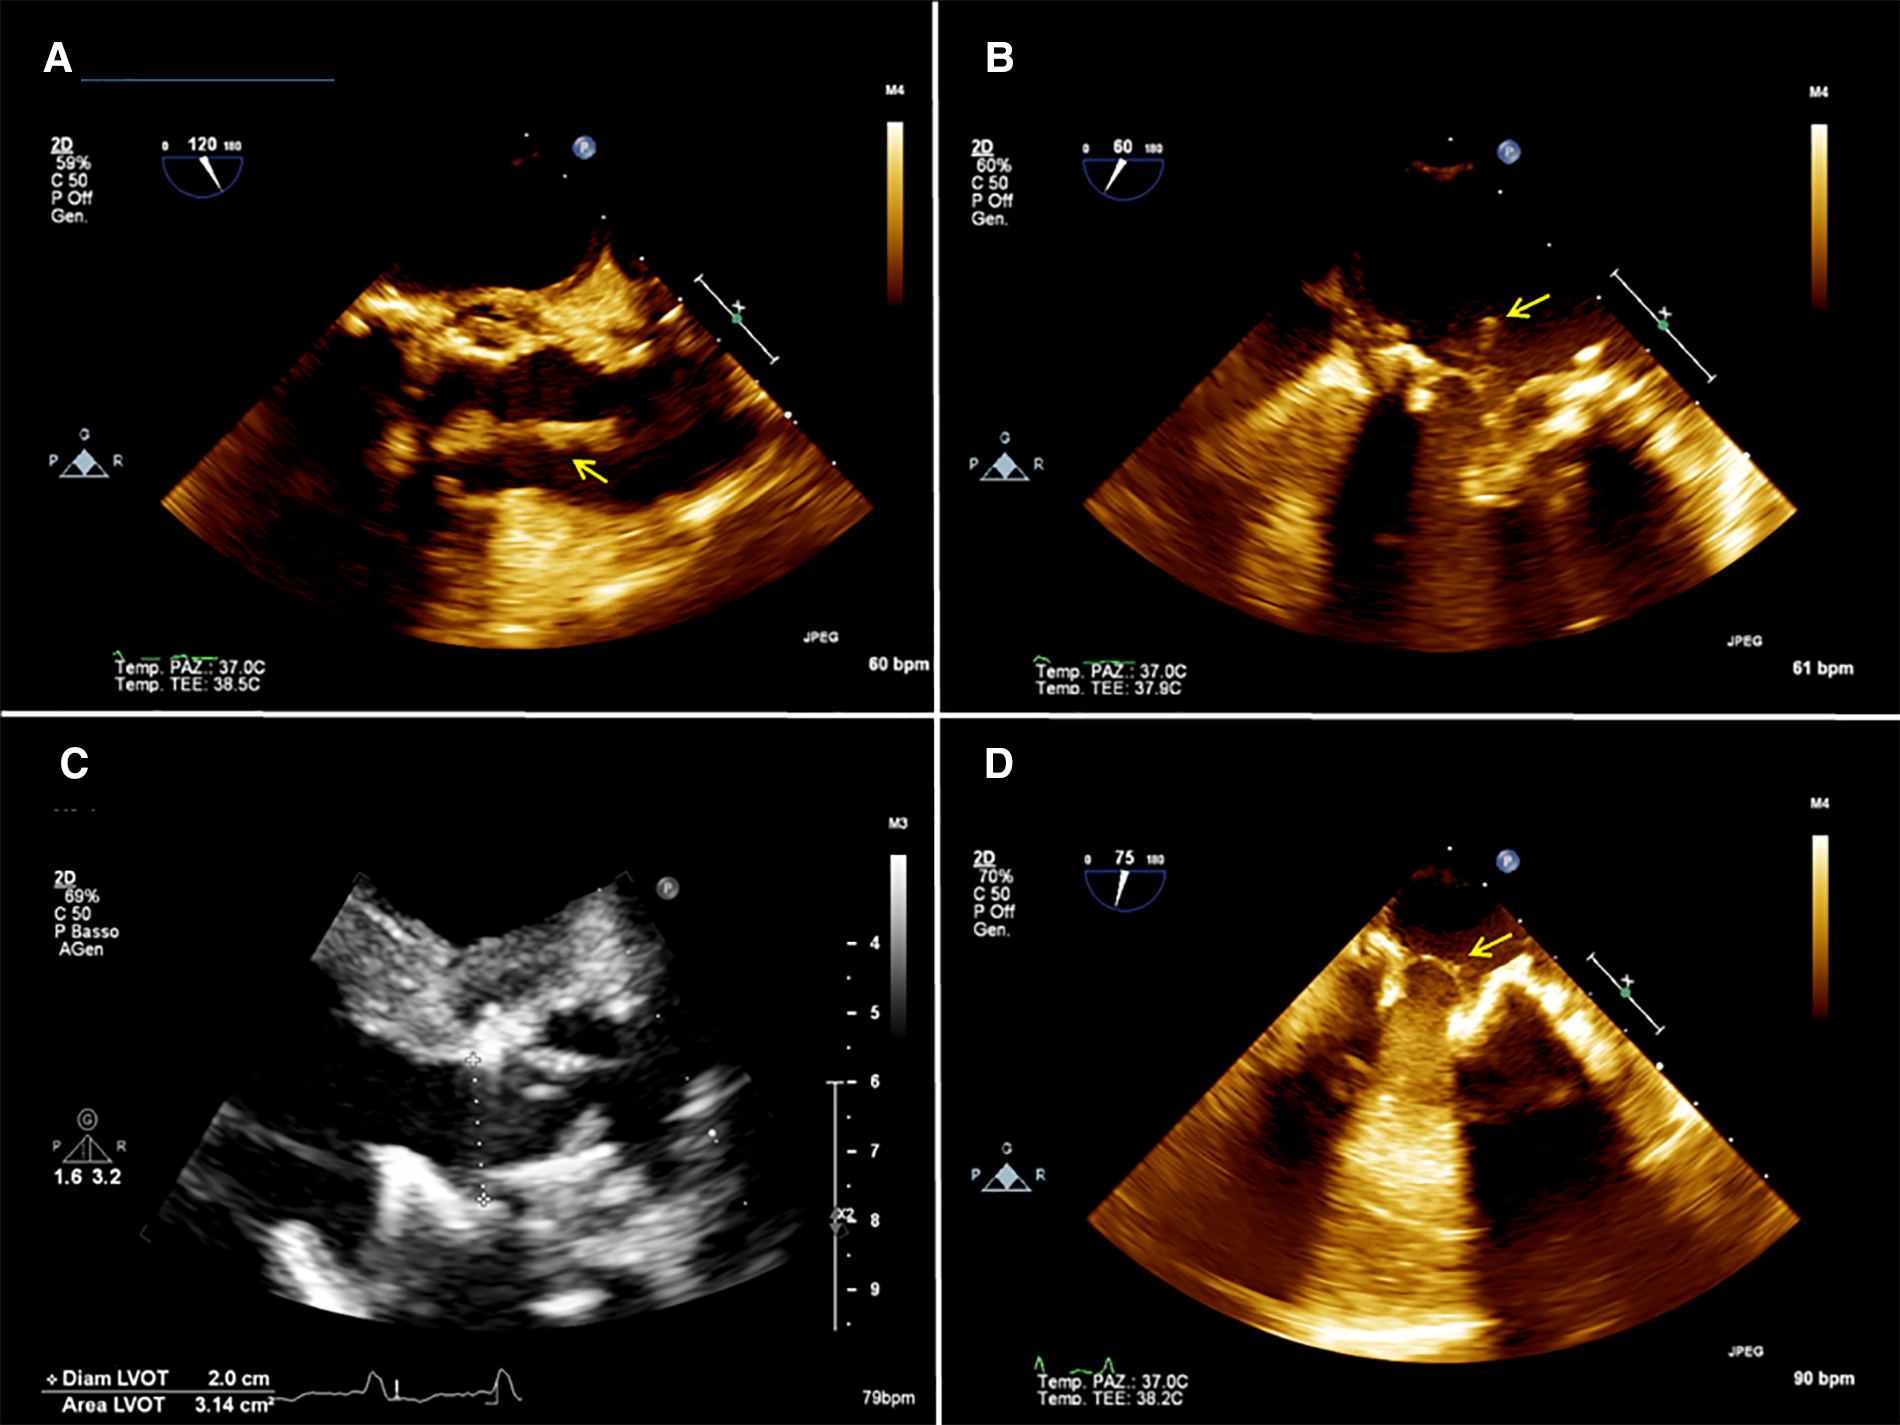

A 54-year-old man with a history of previous aortic valve replacement with a mechanical prosthesis in 2018 and aortic and mitral valve replacement with bioprosthesis, both following valve endocarditis and permanent pace-maker implantation and intravenous (IV) drug abuse was brought to the emergency department for severe asthenia. On physical examination, he was sarcopenic and his vitals were normal. His blood test revealed anemia and kidney dysfunction. Considering his cardiac medical history, he underwent a TTE and a TEE that showed moderate biventricular dysfunction and the presence of vegetation on the mitral and aortic prosthesis with no regurgitation or signs of valve dysfunction (Figures 2A,B). Blood cultures tested positive for Enterococcus Faecalis, and IV antibiotic therapy was started. A total body CT scan showed spleen embolization. Because of the prohibitive risk related to the patient's poor general conditions, the complexity of the potential surgical correction of the disease, and the ongoing IV drug use, the AngioVac system was used to perform aspiration on the patient. A TriGuard was inserted through the left common femoral artery at the beginning of the procedure, then the left subclavian artery was isolated and cannulated with a 16 Fr Biomedicus cannula. The heart apex was exposed and prepared as previously described; a 26 French GORE DrySeal was inserted over a guidewire, and under real-time 2D bi-plane and 3D TTE, the 22 Fr 180° AngioVac cannula was connected to the circuit (with the same setup used for patient 1) and advanced just below the aortic plane and suction was initiated until most of the vegetations disappeared. With real-time 2D bi-plane and 3D TEE guidance, we crossed the mitral prosthesis with the AngioVac cannula; the cannula was bent to 180° and suction was started until satisfactory aspiration of the mitral vegetations was achieved. The final TEE showed no significant residual mass, trivial intraprosthesis aortic, and mitral regurgitation (Figures 2C,D). The procedure was completed as described above. The TriGuard was removed in the standard fashion and small vegetation fragments were found and sent for a culture test. The patient was extubated in the OR, and he did not report any neurological impairment or bowel and limb ischemia. At 1 month, TTE showed partial detachment of the aortic prosthesis with a moderate paravalvular leak (PVL) and absence of new vegetation. Considering the patient's surgical risk and good hemodynamic conditions, we preferred conservative management. Six-month TTE showed no leak progression and no vegetation.

Figure 2

(A) 2D preoperative transesophageal echocardiography (TEE) showing the presence of a mass (arrow) attached to the aortic prosthesis and floating in the aortic root. (B) 2D preoperative TEE showing a mass (arrow) attached to the mitral prosthesis on the atrial side. (C) postoperative 2D TEE showing no residual mass on the aortic prosthesis. (D) postoperative 2D TEE showing a residual minimal stump (arrow) on the mitral prosthesis.